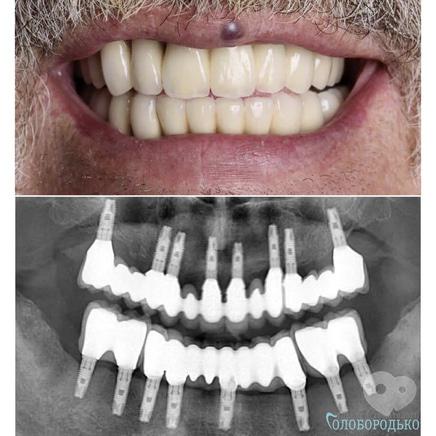

Лікарі нашого центру не просто роблять гарні зуби, вони дарують нову якість життя. Пацієнт звернувся до нас з повною втратою зубів. За допомогою імплантантів та незнімних конструкцій, ми повернули йому втрачений смак до життя !!! На огляді через 3 роки після протезування все стабільно.